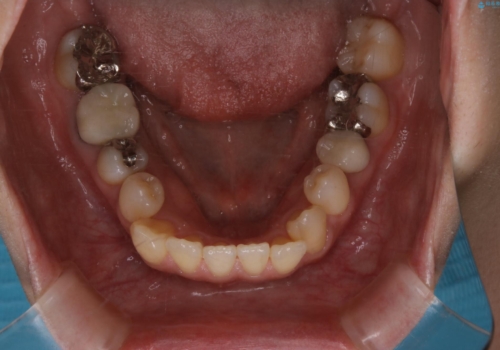

- 上の前歯は内側に入っていることが気になりご相談にいらした方です。インビザラインにて治療を行いました。

1週間でのマウスピース交換を指示していましたが、20時間以上使えない時があると不安との事で、2週間ごとの交換にしていました(実際はほとんど20時間以上使用できていたようです)。治療終了まで時間はかかりましたが、最終的に綺麗に並べることができ、大変喜んでいただけました。